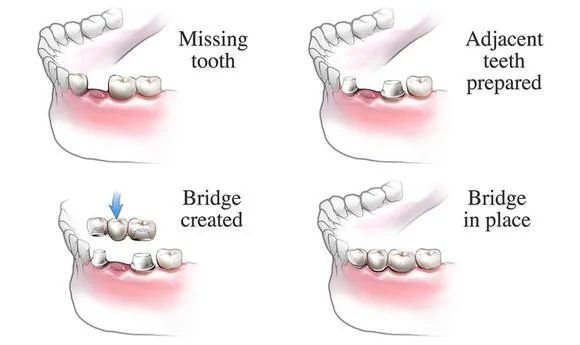

Hollywood Smile is a cosmetic dental procedure that aims to enhance the appearance of the teeth, resulting in a beautiful, radiant smile. It involves a combination of different dental treatments, such as teeth whitening, dental veneers, dental implants, gum contouring, and more. Hollywood Smile can address various concerns, including stained or discolored teeth, misalignment, gaps, chipped or broken teeth, and asymmetry.

The specific procedures involved in a Hollywood Smile vary depending on the individual treatment plan. Generally, the operation may include teeth whitening to achieve a bright base color, dental contouring to reshape and align the teeth, and the placement of veneers or other dental restorations. The dentist will ensure patient comfort throughout the process, and local anesthesia may be administered if necessary.